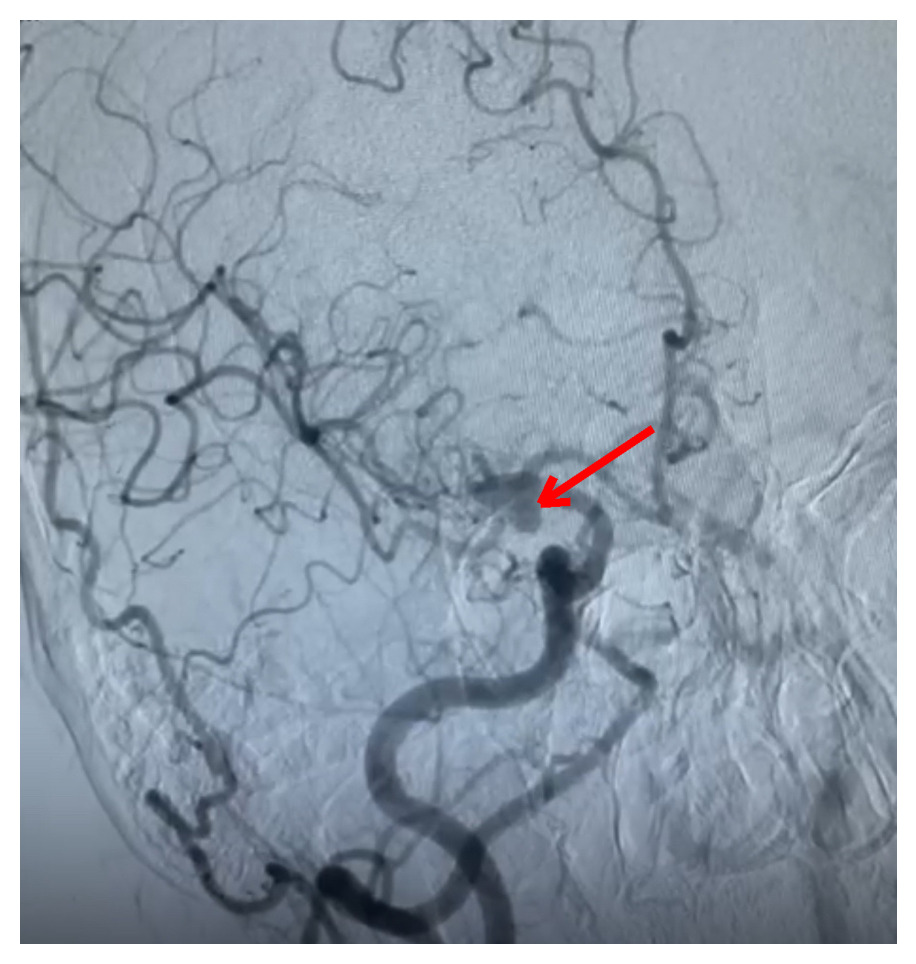

Non-contrast computed tomography (NCCT) of the brain revealed subarachnoid hemorrhage predominantly in the right sylvian fissure [Figure 1]. Hemorrhage grading scales indicated: Modified Fischer Scale 1, Classen Scale 1, and Hijdra Scale 0; indicating minimal blood burden with low risk for delayed cerebral ischemia and vasospasm. These favourable grading parameters not only suggested minimal vasospasm risk but also projected good functional prognosis.

Computed tomography angiography (CTA) revealed an anomalous saccular aneurysm (7×5 mm) arising from the M1 segment of the right middle cerebral artery [Figure 2]. This finding was unusual as the branching artery demonstrated characteristics consistent with orbitofrontal artery territory supply. Digital subtraction angiography (DSA) performed via right femoral approach using a JR 3.5 5F guide catheter confirmed a Type 3 aortic arch with the anomalous aneurysm location [Figure 3]. The aneurysm demonstrated a broad neck and favorable morphology for microsurgical intervention.